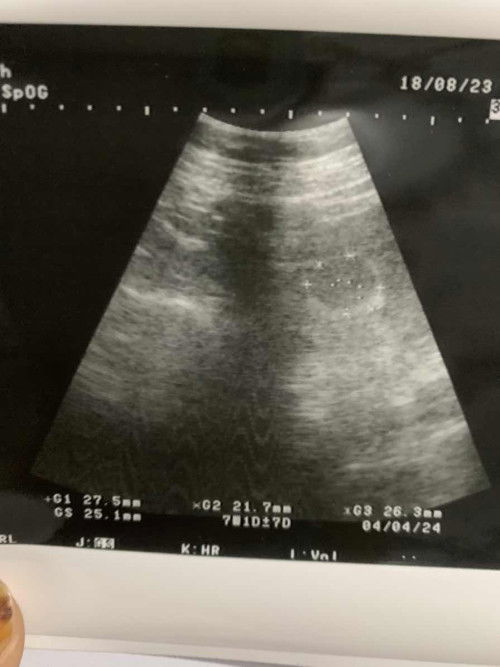

Halo moms . Hpht ku tgl 26juni dan tgl 31juli kemaren aku tastpack garis dua jelas . Kalau di aplikasi udah masuk 5minggu . Dan aku usg perut dan usg transvagina tapi belum terlihat kantung janin seperti gambar . Kata dokter usg lagi 2mingguan . Apakah normal kalau blm terlihat kntung janin? Tapi aku sudah merasakah hamil sprti mual muntah . Mohon Pencerahannya moms #ingintahu #firstmom #firstbaby